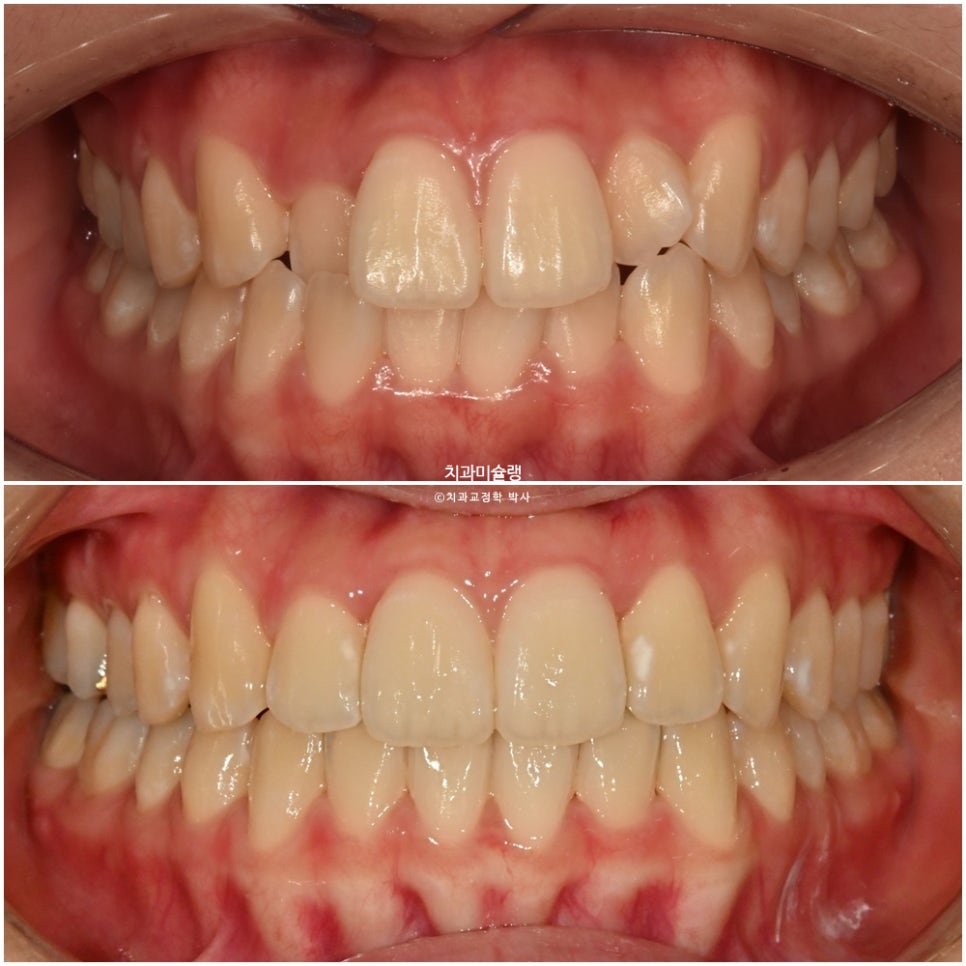

24년 8월 교정치료를 위해 온 환자분입니다. 고치고 싶은것은 돌출, 배열.

측절치가 입천장 쪽으로 들어가 있어 반대교합이 보이며 중심선 불일치가 보입니다.

어금니 교합은 1급으로 좋습니다.

정확히 1년 2개월후, 장치를 다 낀 후 모습입니다. 중심선이나 배열 등은 좋습니다.

중심선은 잘 맞으며

어금니 교합관계는1급이고 잘 물립니다.

2024.08-2026.03

토탈 치료기간은 1년 6개월, 재제작은 1회 했습니다.